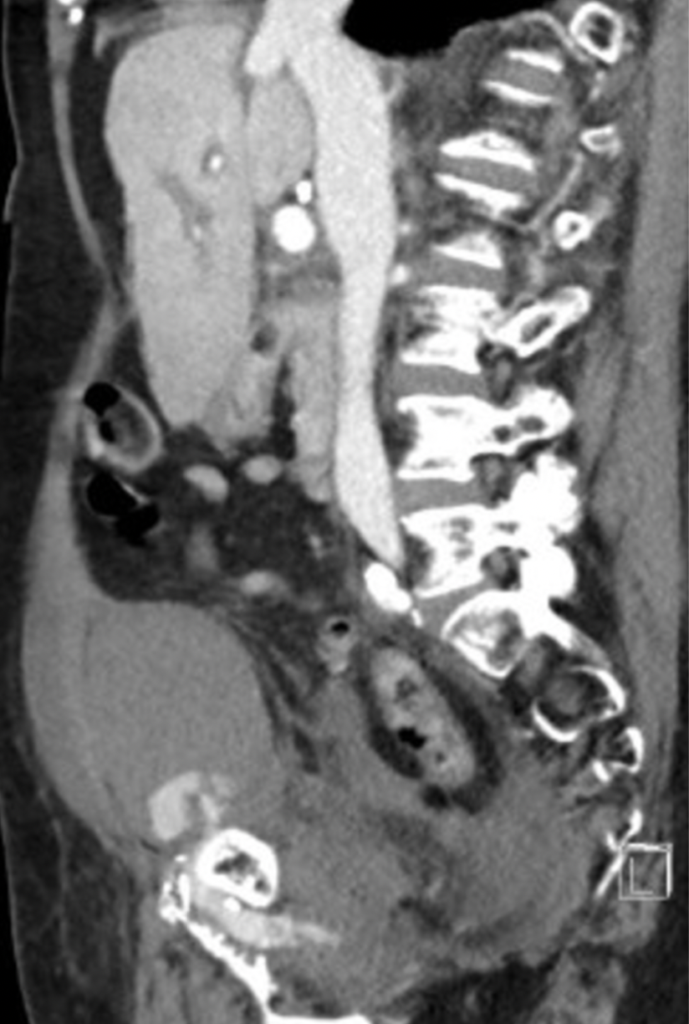

Several hours later, while awaiting admission to the ward, this patient becomes haemodynamically unstable and describes worsening lower pelvic pain.

She is sent for CT scan of the abdomen and pelvis.

Describe and interpret the CT scan